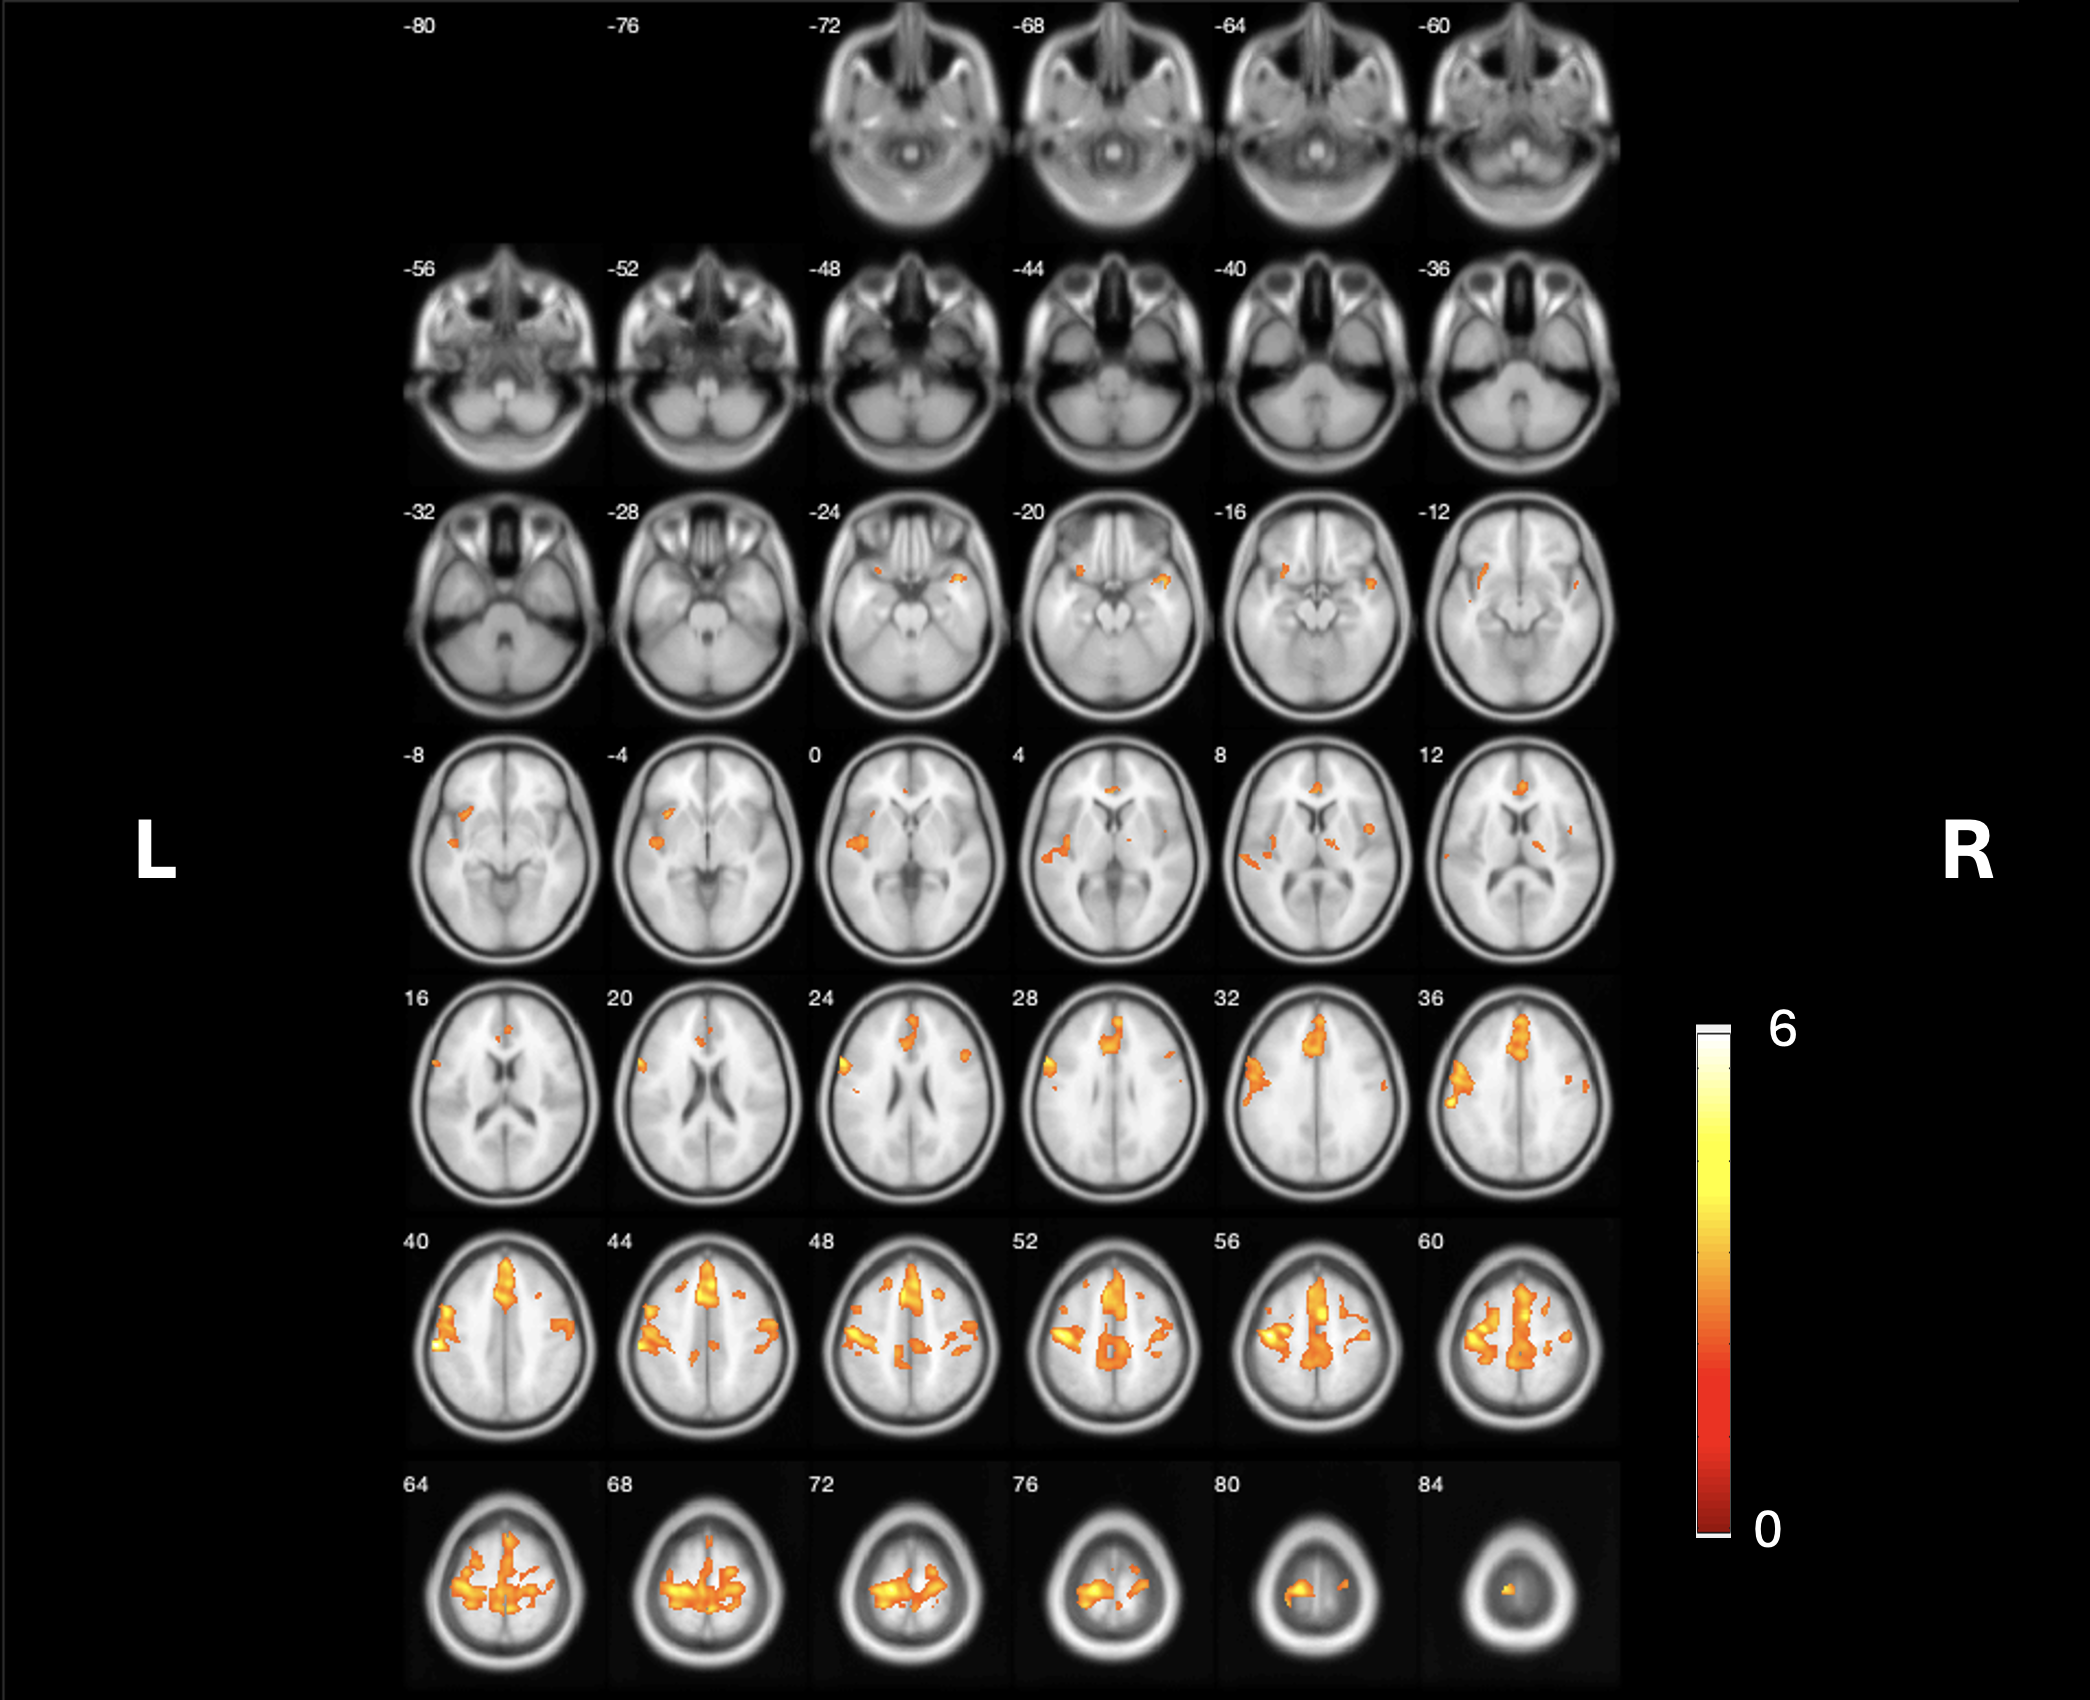

Results: We observed a lower VAChT binding in various cortical and subcortical regions, particularly in the anterior to mid cingulum, left more than right peri-central/SMA regions, and left insula (figure 1; p<0.001;FDR-corrected). No significant associations were found for visual cortical striata, and cerebellar regions and very limited for the thalamus.

Conclusion: The findings indicate that central cholinergic neurotransmission based on VAChT [18F]FEOBV PET imaging, is significantly linked to lower limb stepping VCRT performance, especially in sensorimotor and paralimbic structures. The anterior cingulum and insula play a role in attentional processing, whereas the mid cingulum plays a role in cognitive control, sensory processing, and movement execution.

Figure 1